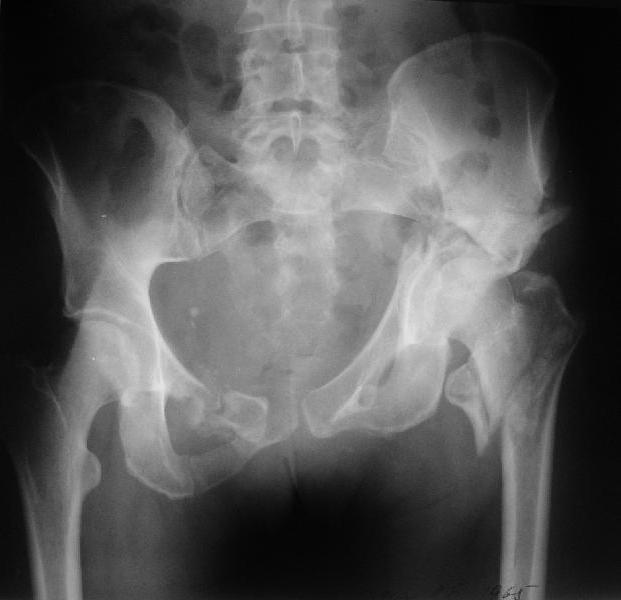

Больная 43 года (промышленный альпинист), 28.07.08 в результате падения с 5 этажа получила политравму:

Перелом свода и основания черепа. Вертикально-нестабильное повреждение таза, осложнённое разрывом мочевого пузыря. Чрезвертельный перелом левого бедра. Перелом правой таранной кости, переломовывих правой кубовидной кости. Тупая травма живота, разрыв печени, ушиб почек. Забрюшинная гематома. В день травмы - лапаротомия, ушивание ран печени. Разрыв мочевого пузыря не диагностирован. Течение болезни осложнилось развитием мочевого затёка и обширной пред- и забрюшинной флегмоны, сформировался свищ мочевого пузыря. 19.8.2008 вскрытие, дренировние флегмоны, ревизия мочевого пузыря, обтурация мочевого свища (свищ закрылся в октябре), 1.10.2008 некрэктомия, пластика по Шеде-Лидскому правой кубовидной кости. По результатам КТ диагностирован рак правой почки (диагностическая находка), 8.10.2008 нефрэктомия справа.

Имеется вертикальное смещение левой половины таза с выраженным отведением крыла (клинически подвижности нет), несросшийся низкий двухколонный перелом левой вертлужной впадины с потерей конгруэнтности, укорочение около5 см, застарелый разрыв лонного сочленения, неправильно сросшиеся переломы обеих ветвей правой лонной кости с укорочением, патологическая подвижность лоно-седалищного фрагмента слева. Правая нижняя конечность неопорна, несмотря на то, что лежа прямую ногу поднимает, ходит на левой ноге (ортопедическая обувь) с костылями, справа тазобедренный ортез. Седалищные нервы работают.Урологи отпустили больную на 6 мес.